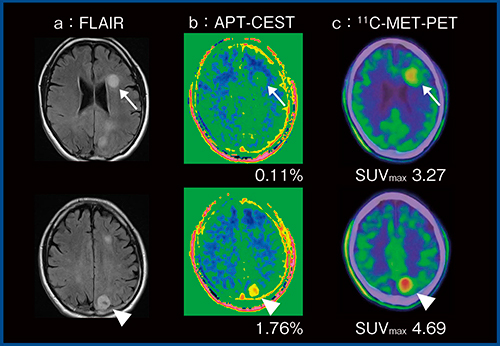

当院における興味深い症例を1例提示する。本症例(図7)は,FLAIR(a)で左の前頭葉(↑)と頭頂葉(△)の2か所に高信号を呈する腫瘤が認められた。造影MRIでは頭頂葉の病変のみ一部濃染が認められ,より悪性度が高いと思われた。しかし,DWIでは前頭葉の病変の方が高信号でADC値も低く,悪性度が高い印象で,判断に迷う結果であった。頭頂葉の病変は,APT CEST(図7 b)ではCEST効果が高く,メチオニンPET(図7 c)でも高集積であり,前頭葉の病変より悪性度が高いと思われた。病理組織学的検査では,前頭葉の病変は退形成性星細胞腫,頭頂葉の病変は膠芽腫であった。APT CESTでは組織内のタンパクの量がCEST効果に反映されるが,メチオニンPETもタンパクを構成するアミノ酸の一つであるメチオニンの組織内への取り込みを見ているため,脳腫瘍の悪性度の評価において,互いに関連している可能性があると思われた。

図7 APT CESTによる悪性度評価